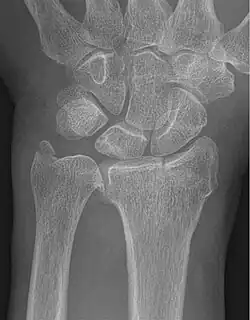

Fracture of the radial styloid process with the fracture line extending into the intraarticular surface

X-ray of a displaced intra-articular distal radius fracture in an external fixator. The articular surface is widely displaced and irregular. This is a Chauffeur's fracture. Frykman class 3.